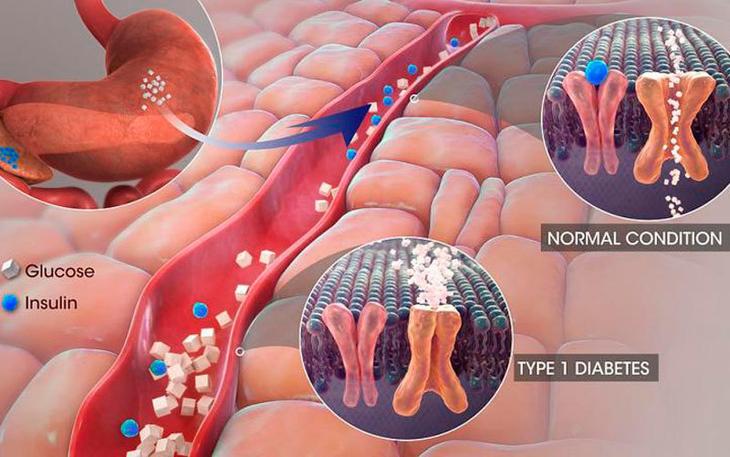

Если летом вы будете отдыхать в странах субтропической или тропической полосы, то с огромной вероятностью местные жители и торговцы рынков будут предлагать вам отведать инжир. Эти маленькие плоды произрастают на низких деревьях и, к примеру, в странах бывшей Югославии, которые на данный момент являются очень популярным туристическим направлением для отдыха на море, в огромном количестве имеются на ветках деревьев диких садов, так что нарвать пакет инжира – легкая задача. Но следует быть осторожным: 5 небольших плодов инжира содержат не менее 150 калорий и примерно 35 граммов сахара. Соответственно, если за день съесть их 10 штук, то по калорийности выйдет эквивалент куриной отбивной, запечённой в сыре, да еще и произойдет опасный сахарный удар по организму! Теперь похвалим данный плод: инжир в большом количестве содержит витамин К и марганец. Однако его употребление должно строго контролироваться во избежание стремительного набора веса. Достаточно сказать, что виноград строго запрещен больным сахарным диабетом, чтобы большинство задумалось, что с виноградом и в самом деле что-то не так. В ста граммах винограда – 65 калорий, а средняя сочная гроздь, так притягивающая глаз, обычно весит 300-400 грамм. Получается, что по калориям она равна яичнице из трех яиц, поджаренной на подсолнечном масле! Еще одной причиной, по которой виноградом можно лишь изредка лакомиться в небольших количествах, является тот факт, что это в высшей степени газообразующий продукт. Так что если вы не хотите набрать вес, а также щеголять с животиком-шариком, мучаясь от натирающих поясков привычной летней одежды, старайтесь обходить виноград стороной.

Достаточно сказать, что виноград строго запрещен больным сахарным диабетом, чтобы большинство задумалось, что с виноградом и в самом деле что-то не так. В ста граммах винограда – 65 калорий, а средняя сочная гроздь, так притягивающая глаз, обычно весит 300-400 грамм. Получается, что по калориям она равна яичнице из трех яиц, поджаренной на подсолнечном масле! Еще одной причиной, по которой виноградом можно лишь изредка лакомиться в небольших количествах, является тот факт, что это в высшей степени газообразующий продукт. Так что если вы не хотите набрать вес, а также щеголять с животиком-шариком, мучаясь от натирающих поясков привычной летней одежды, старайтесь обходить виноград стороной. В 100 граммах вишни содержится 52 калории! Это больше, чем в чашке куриного бульона! А теперь давайте, положа руку на сердце, признаемся: кто остановится, съев всего лишь 100 грамм вишни? Ведь это маленькая горсточка! В результате – легко и непринужденно – можно за раз употребить вишни на столько же калорий, сколько содержится в небольшом свином стейке. Но не будем только ругать эти ягодки с кислинкой. Несколько лет назад учёные из университета Пенсильвании доказали положительный терапевтический обезболивающий эффект вишен. Плоды добавлялись в рацион питания профессиональных спортсменов, и удалось добиться восстановительного эффекта – участвующие в эксперименте отметили, что боль в мышцах и суставах после изнурительных тренировок уменьшилась.